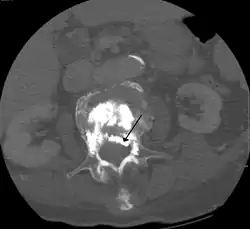

During the procedure, bone cement is injected with a biopsy needle into the collapsed or fractured vertebra. The needle is placed with fluoroscopic x-ray guidance. The cement (most commonly poly methyl methacrylate (PMMA), although more modern cements are used as well) quickly hardens and forms a support structure within the vertebra that provide stabilization and strength. The needle makes a small puncture in the patient's skin that is easily covered with a small bandage after the procedure.[2]

Kyphoplasty is a variation of a vertebroplasty which attempts to restore the height and angle of kyphosis of a fractured vertebra (of certain types), followed by its stabilization using injected bone cement. The procedure typically includes the use of a small balloon that is inflated in the vertebral body to create a void within the cancellous bone prior to cement delivery. Once the void is created, the procedure continues in a similar manner as a vertebroplasty, but the bone cement is typically delivered directly into the newly created void.[3]